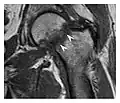

Fatigue fractures are more frequent in women which may be due to the relatively smaller bones of women. Moreover, pregnancy is a well-recognized risk factor for femoral neck fatigue fracture. While fibular and metatarsal fractures have a low risk of complications, other sites including the femoral neck, midanterior tibia, navicular, talar, and other intraarticular fractures are prone to complications such as delayed union, nonunion, and displacement. The site of the insufficiency fracture may be specific to the activity: for example, rugby and basketball players are more prone to navicular fractures, while gymnasts have a higher risk for talar fractures (Figure 7). Long distance runners are at increased risk for pelvic, tibial (Figures 8 and 9), and fibular fractures. In the military, calcaneus (Figure 10) and metatarsals are the most commonly cited injuries, especially in new recruits. Billiard players are at risk for upper limb fractures (Figure 11).[1]

-

a -

b

Figure 7: Fatigue fracture of the talus in a 25-year-old male basketball player with right hind foot and ankle pain, without history of trauma, and a normal initial radiograph (not shown). (a) One-month followup lateral radiograph shows normal appearance. (b) Sagittal T1-weighted MRI shows an irregular fracture line (arrow) within an ill-defined area of hypointensity corresponding to bone marrow edema.[1]